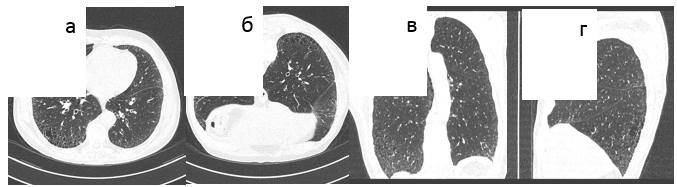

- периферические тракционные бронхо- или бронхиолоэктазы [42] (Рис. 1-3).

Рис. 1. Обычная интерстициальная пневмония, типичная ВРКТ-картина. а) аксиальный срез, б) фронтальная реформация, в) сагиттальная реформация, д) аксиальный срез в положении на животе. Кортикальное распределение изменений с нарастанием их от верхушек к диафрагме, "сотовое легкое", ретикулярные изменения, отсутствие "матового стекла". Исследование в положении на животе подтверждает отсутствие "матового стекла".